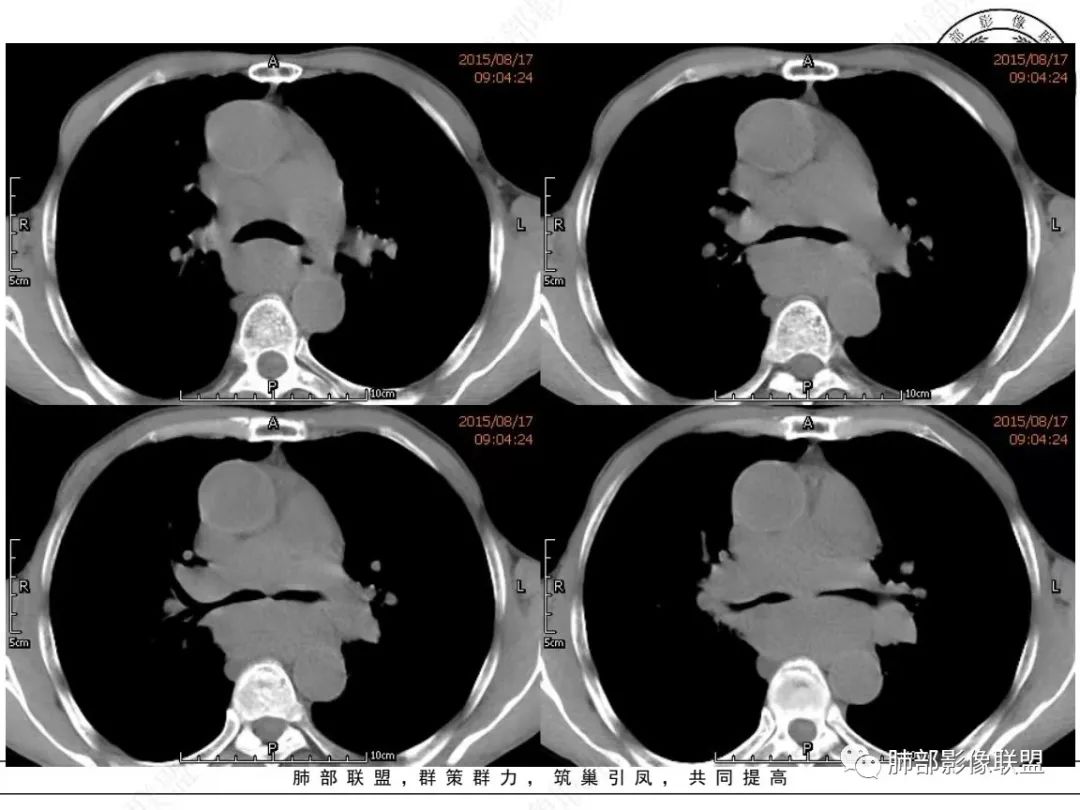

我只是邓较瘦:晨读老年男性,长期吸烟。右肺门、纵隔多发肿大淋巴结、融合成团块,中间支气管、右肺下叶支气管受压变窄,增强扫描强化程度较轻,血管包埋。另两侧腋窝亦见多发肿大淋巴结。常规恶性没问题,小细胞?淋巴瘤?但是於老师的病例总感觉没那么简单。

谢加平:纵隔内中后纵隔及右肺门淋巴结肿大,形成大肿块,整体密度均匀,并轻度强化,见“血管飘浮”征,包绕气管分叉及右主支气管及中间段支气管明显受压狭窄,并包埋右肺门血管束,无侵蚀破坏,右肺动脉后壁见压迹影,右肺下叶背段有阻塞性炎症,首选淋巴瘤,支气管超声内镜活检,明确诊断!

我想CT上,侵袭力强也是特征,破坏力弱表现在血管包绕但形态基本不变,和比较软的感觉。

另外小细胞癌中央区肿块通常没那么圆,有鸭蹼状凸起,周围也不是特别干净,常有小结节或其它阴影

MCL的CT表现为分布无规律的全身多区域淋巴结受侵,少有单一区域淋巴结受累,结外器官受侵多见;MCL有一般NHL淋巴结受累基本CT表现,平扫CT表现为病变密度均匀,受累淋巴结区内呈融合状生长,边界清楚,增强后病灶呈均匀、中等强化,一般病变内无低密度坏死区。确诊需要病理及免疫组化,根据肿瘤组织形态学和免疫组织化学 CD5 及cyclin D1 的表达绝大多数 MCL 可做出明确病理诊。

1.小细胞肺CA:好发吸烟老年男性。常有血液NSE及胃泌素释放肽前体升高。Syn、CgA、CD56阳性。其CT特点可有:冰冻纵隔、冰冻肺门。血管包埋征。针尖样支气管。鸭蹼状凸起。娘小崽大。脂肪间隙消失(常指纵隔及肺门内)。阻塞性炎症不重。侵袭性强。破坏力不强。收缩力弱,内无空泡。沼泽样强化,坏死散而小,坏死不彻底,强化偏低。表面圆钝,角状及条状凸起,蠕虫样表现,腊肠样尾巴(朝肺门侧或背离肺门侧均可以)。胸水多“清澈”(可以理解为淋巴液回流障碍导致的胸水)。点簇状钙化(类似盐与胡椒样)。多见癌性淋巴管炎。另外黄勇老师提出胸膜下的小细胞肺癌具有“山丘征”的特点。